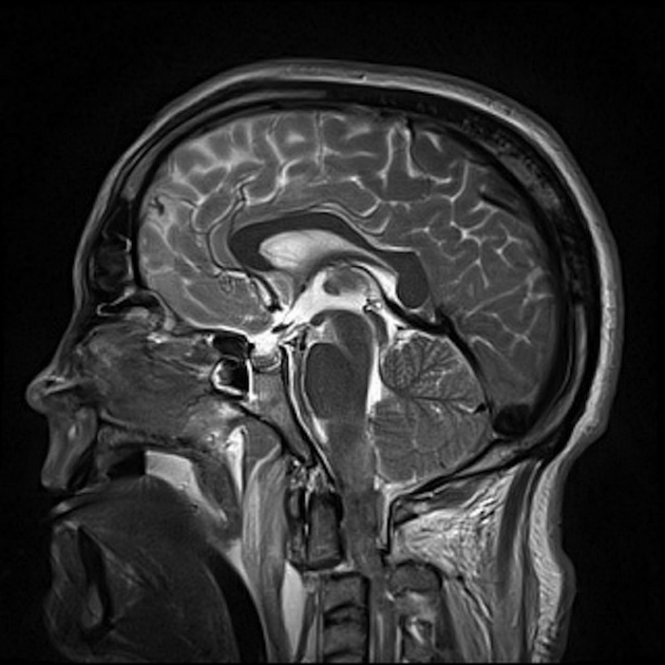

![]() |

| Ảnh X-quang cho thấy đầu của Tony Cowan đã rời khỏi cột sống sau tai nạn - Ảnh: Mirror. |